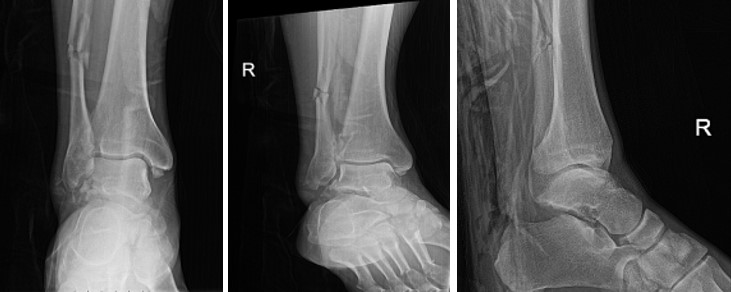

Рентгенографія залишається первинним методом візуалізації. Стандартні проекції включають передньозадню, бічну та mortise-проекцію гомілковостопного суглоба, а також передньозадню, бічну та косу проекції стопи. Додаткова проекція Canale (стопа в положенні підошвового згинання 15°, пронації 15° з направленням променя під кутом 75° до горизонталі) оптимізує візуалізацію шийки таранної кістки.

Компютерна томографія (КТ) є золотим стандартом у діагностиці переломів таранної кістки, дозволяючи детально оцінити характер перелому, ступінь зміщення фрагментів, стан суглобових поверхонь та планувати оперативне втручання. КТ-ангіографія може надати додаткову інформацію про васкулярний статус.